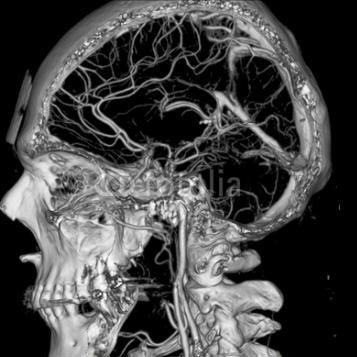

- КТ-ангиография — сканирование системы сосудов в головном мозге рентгенологическим методом с предварительным контрастированием и дальнейшим 3D-моделированием отображения системы кровоснабжения;

Трехмерная (3D) времяпролетная ангиография time-of-flight (TOF) МRА является наиболее распространенным методом, используемым для оценки системы артериального кровоснабжения головного мозга.

МРА 3D TOF обеспечивает более высокий сигнал-шум (signal-to-noise) и короткое время обработки изображений. MРA головного мозга проста в выполнении и не требует контрастного усиления.

Планирование аксиальных 3D – блоков на сагиттальной плоскости; угловое расположение блока должно быть параллельно колену и валику мозолистого тела. Эти срезы должны полностью покрывать Виллизиев Круг от уровня мозолистого тела до уровня большого затылочного отверстия.

MP-ангиография, проведенная на уровне артериального круга мозга, позволяет визуализировать внутренние сонные и средние мозговые артерии, проксимальные отделы передних мозговых артерий, основную и задние мозговые артерии. Передние и задние соединительные артерии, а также дистальные отделы мозговых артерий не определяются из-за малого их диаметра.

МРА позволяет обнаружить патологические изменения магистральных сосудов головного мозга: извитость с петлеобразованием и обеднение периферического сосудистого рисунка передней, средней и задней мозговых артерий (ПМА, СМА, ЗМА) с обеих сторон. При тромбозе на МРА определяется «обрыв» сосуда и не визуализируются ветви сосудов, расположенные дистальнее окклюзии.

При стенозе артерии выявляют равномерное или неравномерное сужение сосуда в определенном сегменте, в то же время при гипоплазии артерии в основном обнаруживают равномерное сужение сосуда на всем протяжении.